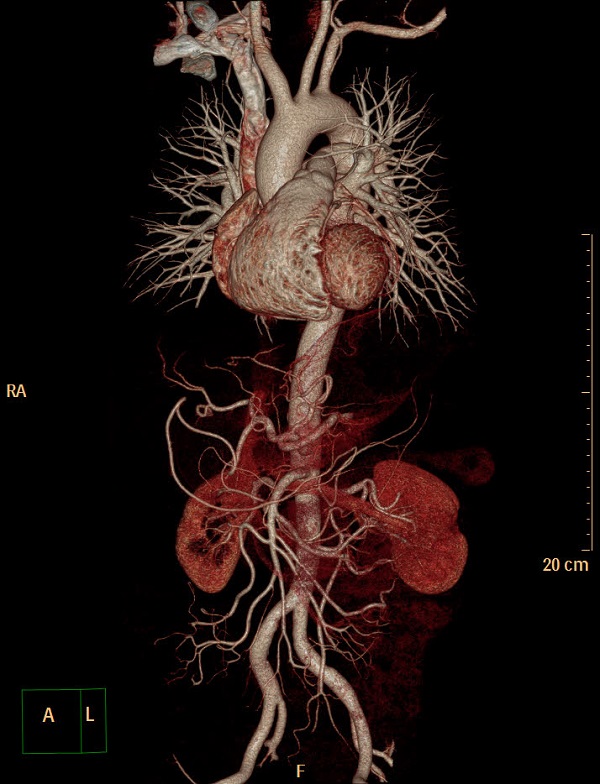

近日,中国科学院合肥肿瘤医院医学影像中心放射影像科成功开展了胸痛三联CTA一站式扫描,整个扫描过程仅耗时10秒钟,高效的诊断为患者争取了最佳救治时机,也为临床后续治疗提供了强有力支撑。 目前该项新技术仅在少数三甲医院开展,处于国内先进水平。

常规临床上疑患者胸痛三联,传统方法需要分3次独立实施冠状动脉、肺动脉、主动脉CTA检查。一是耗时长,遇到肾脏功能不好的患者,需要等待多天才能完成该3项检查;二是需住院等候或多次排队往返,多次注射药剂,综合费用高;三是对患者身体影响大,多次注射造影剂、反复接受CT检查,增加了病人受辐射剂量和造影剂用量。而“胸痛三联征一站式 CTA”检查,只需注射一次造影剂,一次扫描,即可同时获得冠状动脉、肺动脉及胸主动脉影像,还能实时了解肺部情况,不仅缩短了检查时间,又为患者节约了检查费用、减少造影剂用量及辐射剂量。

11月16日,在放射影像科科主任周燕飞及副主任医师季必勇的牵头努力下,放射影像科团队经过反复调试修改扫描参数,成功开展了一站式扫描。整个扫描过程10秒,不仅减少了患者辐射剂量,缩短扫描时间,减少了造影剂剂量对肾脏的毒性作用,同时节省了患者的重复检查。

一站式多脏器再现成像